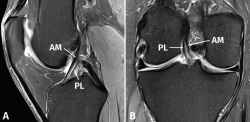

El LCA se origina en el margen medial del cóndilo femoral lateral y está formado por 2 fascículos bien diferenciados, denominados anteromedial (AM) y posterolateral (PL), en función de sus inserciones tibiales(1)(Figura 1).

Figura 1. Anatomía normal del ligamento cruzado anterior (LCA). Esquemas sagital (A) y coronal (B) que ilustran la anatomía fascicular del LCA. AM: fascículo anteromedial; PL: fascículo posterolateral.

Estudios biomecánicos han demostrado que ambos haces contribuyen de forma sinérgica a la estabilidad de la rodilla en todo el rango de movimiento de la articulación. Sin embargo, cada fascículo tiene una función diferente: las fibras del fascículo AM se tensan en flexión, mientras que las fibras del fascículo PL se tensan en extensión limitando la traslación tibial anterior. El fascículo PL tiene también una función importante en la restricción de la rotación tibial(1,2).